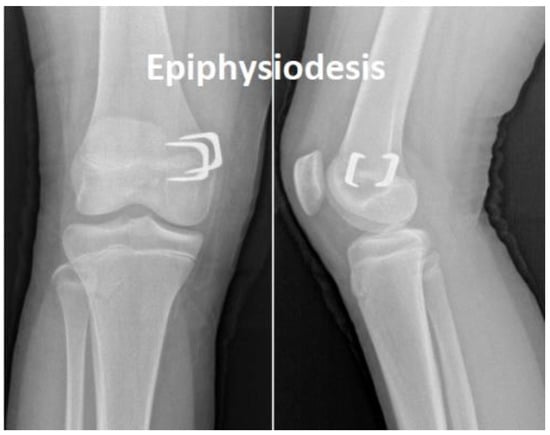

Using staples, the physis (epiphyseal plate) can be relatively simply restrained either on both sides when correcting limb length discrepancy (i.e., “epiphysiodesis”) or only on one side when correcting angular deformities (i.e., “hemiepiphyseodesis”) (see Figure 1 and Figure 2). Unlike the irreversible method of permanent epiphysiodesis, see [8], epiphyseal stapling does not destroy the epiphyseal plate and, therefore, allows resumption of the growth once the optimal correction is achieved; see [4].

According to [1,4], besides accurate diagnosis confirmed by a radiogram of the whole limb (see Figure 2), good timing of the treatment is also very important. The surgical procedure involves a short longitudinal incision through soft tissues over the physis and extraperiosteal implantation of the staple using a special instrument under radiography control [11] (see Figure 3). The staple must bridge the physis but not penetrate it to prevent its impairment (see Figure 4).

Figure 4. Position of staples bridging the physis in femur.